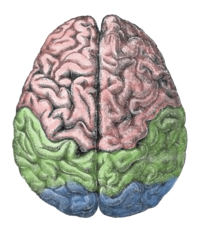

New Delhi, Feb 26 (IBNS): A diet created by researchers at Rush University Medical Center may help substantially slow cognitive decline in stroke survivors, according to preliminary research presented on Jan. 25 at the American Stroke Association’s International Stroke Conference 2018 in Los Angeles.